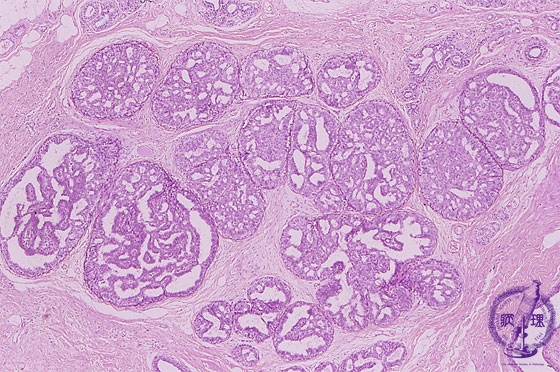

Microscopic image(HE stain, low power view):Ductal hyperplasia. Proliferating epithelium filled peripheral ducts. The differential diagnosis from carcinoma can be difficult, especially when the biphasic patterns are unclear.